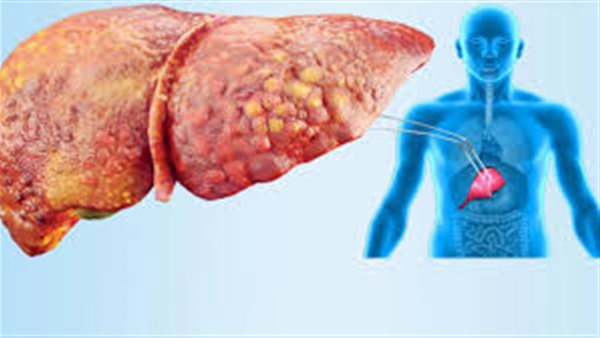

يصيب مرض الكبد الدهني غير الكحولي (NAFLD) ملايين الأشخاص حول العالم، وغالبًا ما يتطور في صمت، قد لا يظهر في بداياته أي أعراض واضحة، لكن إذا تُرك دون تدخل، يمكن أن يتطور إلى تليف الكبد، وقد تكون هذه الحالة قاتلة.

3 مشروبات شائعة تسرع تطور الكبد الدهني

ويجب معرفة المشروبات التي تشكل خطورة على صحة الكب، والغريب في الأمر أن بعض المشروبات اليومية قد تكون من أكثر العوامل تسريعًا لهذا التدهور، والكحول ليس واحدًا منها، بخلاف مشروب الكحول هناك 3 مشروبات شائعة تدمر صحة الكبد يجب الابتعاد عن تناولها.